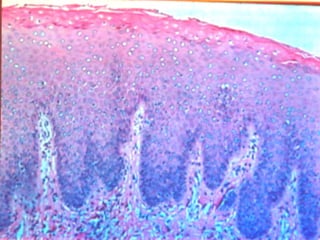

This document discusses benign and malignant diseases of the vulva. It begins by outlining common symptoms of vulvar diseases such as itching, burning, and bleeding. It then provides an overview of the general pathology and terminology used to describe vulvar diseases. The document categorizes vulvar lesions as white, red, or brown/bluish and discusses specific conditions that present with each color, including vitiligo, lichen sclerosis, squamous cell hyperplasia, infections, dermatitis, and various precancers and cancers. Treatment options are provided for some conditions like HPV. Throughout, it emphasizes the importance of inspection, palpation, biopsy prior to treatment, and using medical therapy for benign lesions.